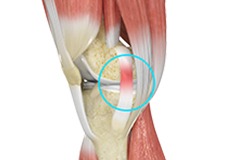

Jumper's Knee

Jumper’s knee, also known as patellar tendinitis, is inflammation of the patellar tendon that connects your kneecap (patella) to your shinbone. This tendon helps in the extension of the lower leg.